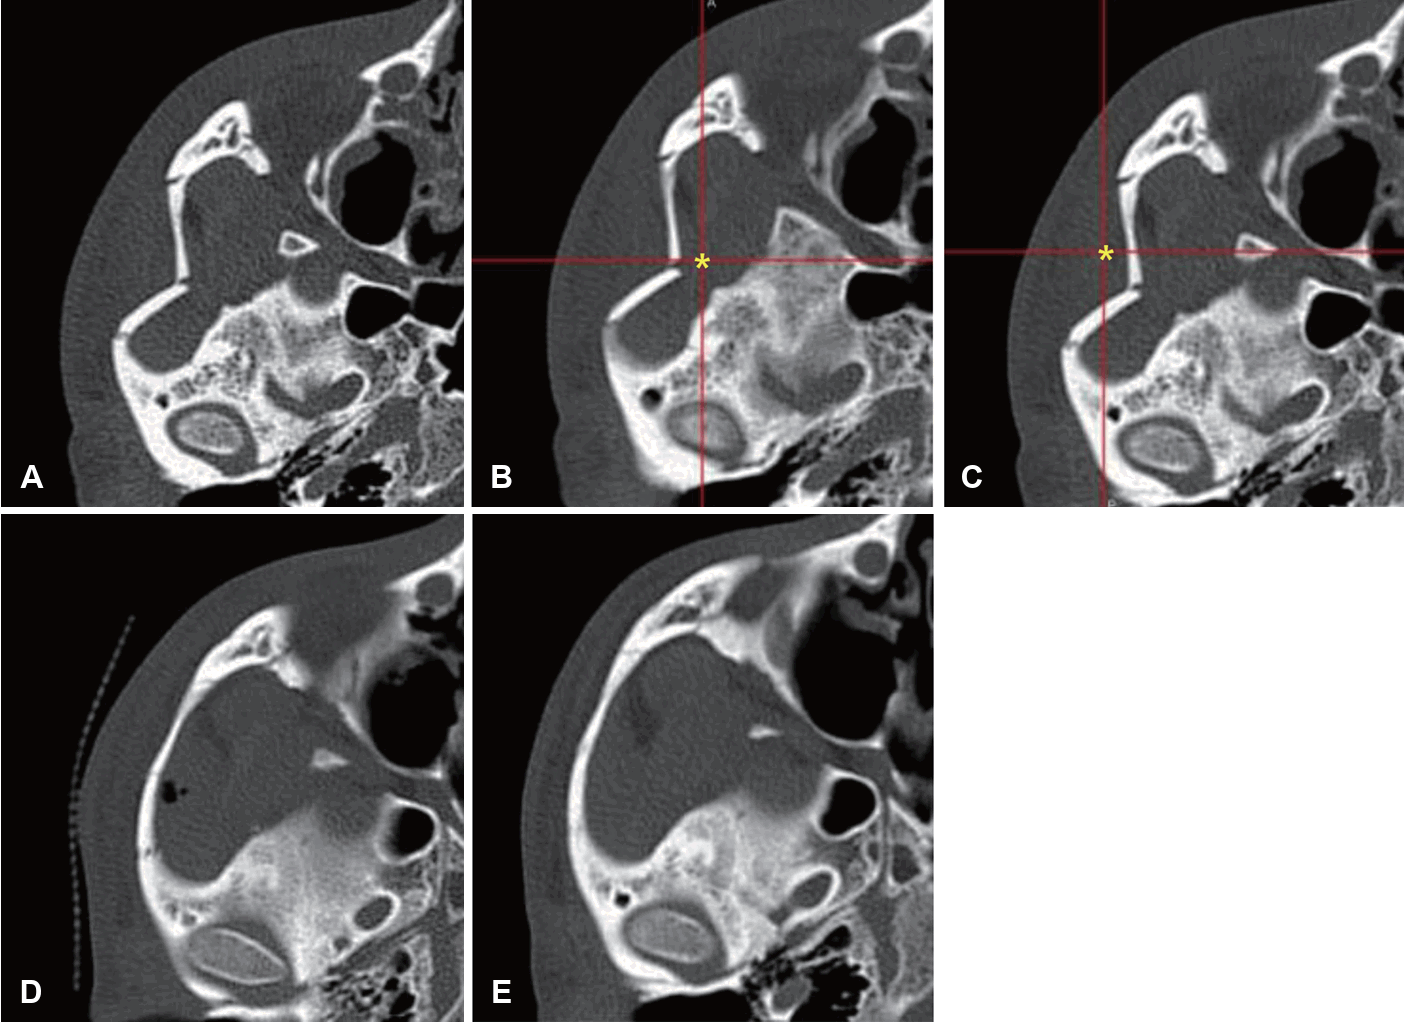

모든 환자는 외상 후 평균 8.12일, 최저 1일에서 최고 34일에 수술을 받았으며, 수술 시간은 평균 43.6분이었다. 수술은 영상유도수술 시스템을 접목한 Gillies 접근법으로 시행되었으며, 모든 증례에서 정복 기구의 삽입 위치 및 골절편의 정복 상태를 수술 중에 실시간으로 확인하였다(Fig. 2).

Representative case. A: Preoperative axial CT. B: Intraoperatively, the navigation pointer is indicating the most depressed area (asterisk) of the zygomatic arch. C: Intraoperatively, the navigation pointer is indicating the position of the reduced zygomatic arch (asterisk) after reduction. D: Immediate postoperative axial CT. E: Postoperative 3-month axial CT with good alignment.

수술 전 개구 장애가 있었던 환자 13예 전원에서 수술 후 증상이 해소되었으며, 안면 신경 마비나, 감염 등의 수술 관련 합병증은 관찰되지 않았다. 또한 정복 실패로 인한 재수술 사례도 없었다. 안면부 3차원 전산화단층촬영을 통해 평가한 정복 결과는 good은 19예, moderate는 6예, poor는 0예였다(Fig. 3).